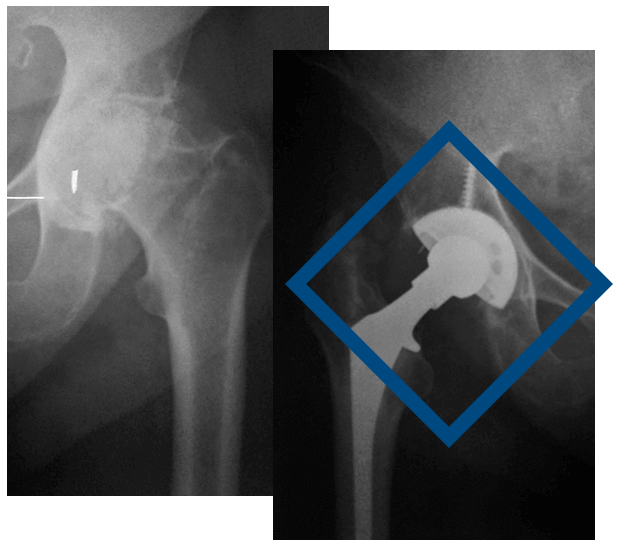

Η αρθροπλαστική ισχίου είναι η επέμβαση κατά την οποία αντικαθίστανται οι κατεστραμμένες επιφάνειες της άρθρωσης του ισχίου με τεχνητά εμφυτεύματα.

Προετοιμάζοντας την εγχείρηση ο ιατρός θα λάβει αναλυτικά το ιατρικό ιστορικό σας και θα προβεί σε αιματολογικές εξετάσεις, ακτινογραφίες και καρδιογράφημα που θα επιβεβαιώσουν ότι δεν διατρέχετε κάποιο κίνδυνο και είστε ασφαλής να εγχειριστείτε. Κατά τη διάρκεια της επέμβασης αφαιρείται η μηριαία κεφαλή του ισχίου και αντικαθίσταται από τεχνητή άρθρωση. Αυτή, αποτελείται από δύο μέρη: ένα μεταλλικό στέλεχος (στειλεός) με μια μεταλλική κεφαλή στην άκρη του και που εφαρμόζεται στο μηριαίο οστό και ένα ένθεμα σαν μικρό κυπέλλιο κατασκευασμένο από πολυαιθυλένιο (πλαστικό) που περιβάλλεται από μεταλλικό κέλυφος και εφαρμόζει στην κοτύλη. Για την σταθερή στήριξη των τεχνητών αυτών μερών, μπορεί να χρησιμοποιηθεί ειδικό ακρυλικό τσιμέντο οστών. Σε νεότερους ασθενείς ή σε ασθενείς που δεν έχουν προβλήματα οστεοπόρωσης μπορεί να επιτύχουμε την ενσωμάτωση του μετάλλου με το οστό χωρίς τσιμέντο (τεχνική press fit) , που μπορεί να μας προσφέρει μεγαλύτερη διάρκεια ζωής. Ένας τρίτος, μεικτός τρόπος (υβρίδιο), αφορά την εφαρμογή τσιμέντου στο μηριαίο στέλεχος αλλά όχι στην κοτύλη.

Η επέμβαση γίνεται συνήθως με ραχιαία ή επισκληρίδιο αναισθησία. Κατά τη διάρκεια της επέμβασης, η οποία διαρκεί περίπου 1 ½ – 2 ώρες, αφαιρείται η κεφαλή του μηριαίου οστού και αντικαθίσταται από τεχνητή άρθρωση. Η κεφαλή του μηριαίου κόβεται και αφαιρείται ενώ στη θέση της τοποθετείται ένα μεταλλικό στέλεχος (στειλεός) στο οποίο προσαρμόζεται μια μεταλλική κεφαλή. Η κατεστραμμένη κοτύλη αντικαθίσταται από ένα κυπέλλιο από ειδικό πλαστικό που περιβάλλεται από μεταλλικό κέλυφος το οποίο εφαρμόζει στην κοτύλη.Το υλικό των μεταλλικών μερών της άρθρωσης αποτελείται από ανοξείδωτο χάλυβα, τιτάνιο ή κράμα κοβαλτίου – χρωμίου. Υπάρχουν και κεραμικές προθέσεις με καλύτερα χαρακτηριστικά τριβής αλλά είναι πιο εύθρυπτες. Η χρησιμοποίηση του πλαστικού γίνεται διότι προσφέρει μικρότερο συντελεστή τριβής με την μεταλλική κεφαλή.